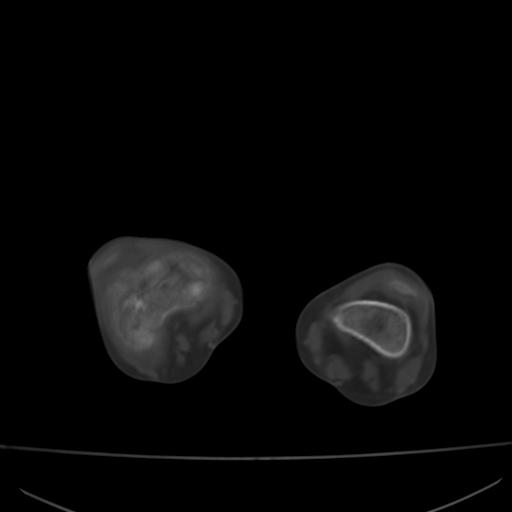

标题: PED0940:M12Y,左股骨下端酸痛畸形 [打印本页]

标题: PED0940:M12Y,左股骨下端酸痛畸形

12岁男孩,左膝关节肿痛8年,近月明显

内生骨软骨瘤?

血友性关节病?